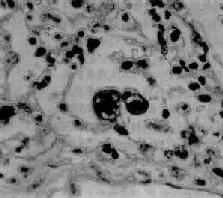

图9-21 腺病毒肺炎 图中央可见肿大肺泡上皮细胞中的核内包含体 有些混合感染,如麻疹病毒合并腺病毒感染,特别是又继发细菌感染的病毒性肺炎,病变更为严重,肺炎病灶可呈小叶性、节段性或大叶性分布。支气管和肺组织明显坏死、出血,并可混杂化脓性病变,从而掩盖了病毒性肺炎原来的病变特征。 (三)支原体肺炎 支原体肺炎(mycoplasmal pneumonia)是由肺炎支原体(mycoplasma pneumoniae)引起的一种间质性肺炎。支原体系介于细菌和病毒之间的微生物,共有30余种,其中多种可寄生于人体,但不致病,仅有肺炎支原体能引起呼吸道疾病。各种肺炎中约有5%~10%乃由肺炎支原体引起。主要经飞沫感染,秋、冬季节发病较多,儿童和青年发病率较高,通常为散发性,偶尔流行。患者起病较急,多有发热、头痛、咽痛及剧烈咳嗽(常为干性呛咳)等症状。胸部检查,可闻干、湿啰音。X线检查,肺部呈段性分布的纹理增加及网织状阴影。白细胞计数有轻度升高,淋巴细胞和单核细胞增多,痰、鼻分泌物及咽喉拭子能培养出肺炎支原体。 【病理变化】 肺炎支原体感染可引起整个呼吸道的炎症。肺部病变常仅累及一个肺叶,以下叶多见。病变主要发生于肺间质,病灶呈段性分布,暗红色,切面可有少量红色泡沫状液体溢出。气管或支气管腔内也可见粘液性渗出物。胸膜光滑。镜下,病变区域肺泡间隔明显增宽,有大量淋巴细胞、浆细胞和单核细胞浸润,肺泡腔内无渗出物或仅有少量混有单核细胞的浆液性渗出液。小支气管和细支气管壁及其周围组织也常有炎性细胞浸润。重症病例,上皮亦可坏死脱落,往往伴有中性粒细胞浸润。支原体肺炎预后良好。死亡率在0.1%~1%之间。